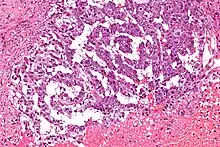

| Micrograph showing the yolk sac component of a mixed germ cell tumour. H&E stain. | |

Endodermal sinus tumor (EST) is a member of the germ cell tumor group of cancers.[1] It is the most common testicular tumor in children under three,[2] and is also known as infantile embryonal carcinoma. This age group has a very good prognosis. In contrast to the pure form typical of infants, adult endodermal sinus tumors are often found in combination with other kinds of germ cell tumor, particularly teratoma and embryonal carcinoma. While pure teratoma is usually benign, endodermal sinus tumor is malignant.

The histology of EST is variable, but usually includes malignant endodermal cells. These cells secrete alpha-fetoprotein (AFP), which can be detected in tumor tissue, serum, cerebrospinal fluid, urine and, in the rare case of fetal EST, in amniotic fluid. When there is incongruence between biopsy and AFP test results for EST, the result indicating presence of EST dictates treatment.[3] This is because EST often occurs as small "malignant foci" within a larger tumor, usually teratoma, and biopsy is a sampling method; biopsy of the tumor may reveal only teratoma, whereas elevated AFP reveals that EST is also present. GATA-4, a transcription factor, also may be useful in the diagnosis of EST.[4]

EST can have a multitude of morphologic patterns including: reticular, endodermal sinus-like, microcystic, papillary, solid, glandular, alveolar, polyvesicular vitelline, enteric and hepatoid.

Schiller–Duval bodies on histology are pathognomonic and seen in the context of the endodermal sinus-like pattern. Rarely, it can be found in the vagina.[6][7]